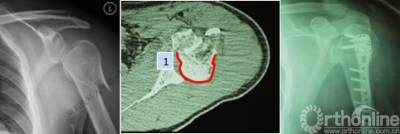

1.X线片

2.肩关节CT

确定肩关节后脱位。

了解反Hill-sachs损伤和程度。

观察肱骨近端主要骨折线和次要骨折线及形态。

Ⅱ型: +肱骨颈骨折+小结节骨折(病例3)。